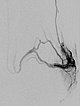

Digital subtraction angiography, with the catheter in the left superior gluteal artery, reveals multiple, barely identifiable small arteriovenous fistulas typical of the diffuse arteriovenous malformations seen in Parkes-Weber syndrome.

Superselective digital subtraction angiography via a microcatheter in the superior gluteal artery in a distal branch. The nidus of the fine fistulous arteriovenous malformation shows such fine shunts that they can hardly be resolved anatomically on angiography.